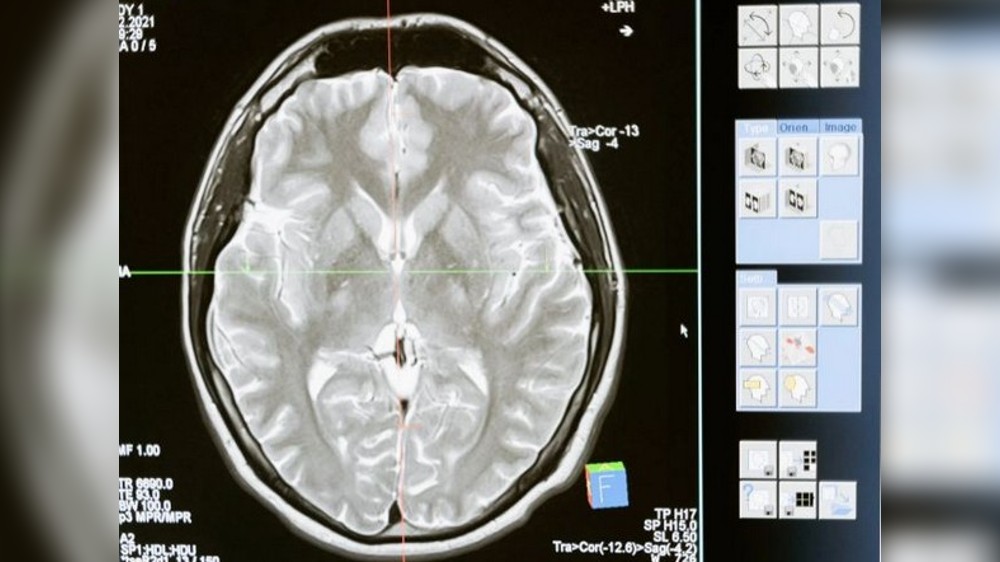

Neural networks: Human brain has dizzying array of mystery cells

NEW YORK: An international team of scientists has mapped the human brain in much finer resolution than ever before. The brain atlas, a $375 million...